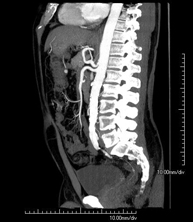

Prueba diagnóstica no invasiva que consiste en el estudio de la arteria aorta abdominal obteniendo imágenes de alta definición anatómica mediante el empleo de un equipo de TC (Tomografía Computarizada) y de contraste yodado. La calidad de las imágenes permite realizar reconstrucciones en 2D y 3D gracias a estaciones de trabajo especializadas en el estudio arterial. Está indicado en aquellos pacientes con enfermedad vascular (aterosclerosis), en aneurismas de aorta, en pacientes con dolor abdominal de posible origen vascular, en estudios pre-quirúrgicos de lesiones adyacentes a la aorta abdominal como "mapa" vascular, etc. La información obtenida de forma no invasiva es indispensable para los pacientes que requieren tratamiento percutáneo o quirúrgico. En aquellos pacientes que solo requieren un seguimiento de las lesiones vasculares, esta técnica es la técnica no invasiva de elección junto con la angio-RM. - Angio-TC arterias renales

Prova diagnòstica no invasiva que consisteix en l'estudi de l'artèria aorta abdominal amb l'obtenció d'imatges d'alta definició anatòmica mitjançant l'ús d'un equip de TC (Tomografia Computaritzada) i contrast iodat. La qualitat de les imatges permet realitzar reconstruccions en 2D i 3D gràcies a estacions de treball especialitzades en l'estudi arterial. Està indicat en aquells pacients que pateixen malaltia vascular (arteriosclerosi), aneurismes d'aorta, en pacient amb dolor abdominal d'un possible origen vascular, en estudis prequirúrgics de lesions adjacents a l'aorta abdominal com el "mapa" vascular, etc. La informació obtinguda de forma no invasiva és indispensable per als pacients que requereixen tractament percutani o quirúrgic. En aquells pacients que només requereixen un seguiment de les lesions vasculars, aquesta tècnica és la tècnica no invasiva d'elecció juntament amb l'angio RM. - Angio TC d'artèries renals